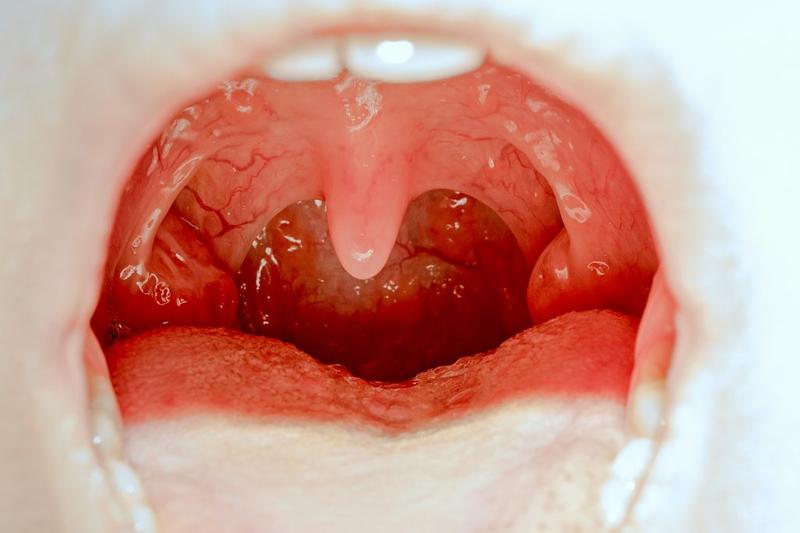

Przerost trzeciego migdała, znanego także jako migdałek gardłowy, stanowi problem, który dotyka wiele dzieci, zwłaszcza w wieku przedszkolnym. Gdy ten drobny, ale kluczowy element układu odpornościowego powiększa się, pojawia się szereg nieprzyjemnych objawów. Obserwując swoje dziecko, warto zwracać uwagę na symptomy, mogące sugerować przerost migdałka, takie jak oddychanie przez usta, chrapanie oraz nawracające infekcje. Dzięki właściwemu rozpoznaniu objawów zapewniamy sobie szybszą interwencję oraz skuteczniejsze leczenie.

Oddychanie przez usta to jeden z najczęściej występujących objawów przerostu trzeciego migdała. Dziecko, które ma powiększony migdałek, często trzyma otwartą buzię; można to zauważyć zarówno w ciągu dnia, jak i podczas snu. W nocy dodatkowo mogą występować dolegliwości, takie jak chrapanie i bezdechy, które są szczególnie groźne. Ponadto inne symptomy, sugerujące problem z migdałkiem, to przewlekły katar, częste zapalenia uszu oraz nosowe brzmienie głosu. Wszystkie te dolegliwości mogą prowadzić do dalszych komplikacji, jak niedosłuch czy zaburzenia mowy.

Trzeci migdał, czyli migdałek gardłowy, pełni ważną rolę w układzie odpornościowym, chroniąc organizm przed wirusami i bakteriami. W przypadku większości dzieci migdał ten pozostaje niewielki i nie powoduje żadnych problemów. Niemniej jednak u niektórych maluchów może wystąpić przerost tego migdała, szczególnie w okresach intensywnego kontaktu z infekcjami wirusowymi czy bakteryjnymi. Ten przerost obserwuje się zwłaszcza u dzieci w wieku przedszkolnym, kiedy ich system immunologiczny zmaga się z licznymi patogenami, co niestety może prowadzić do poważnych problemów zdrowotnych.

Rodzice powinni zwrócić szczególną uwagę na objawy, które mogą wskazywać na konieczność wizyty u laryngologa. Przede wszystkim warto obserwować, czy dziecko oddycha przez usta, chrapie w nocy, ma nawracające infekcje dróg oddechowych oraz problemy ze słuchem. Dodatkowo, dzieci z przerostem trzeciego migdała często mają zmienioną barwę głosu, trudności z przełykaniem oraz mogą doświadczać kłopotów z koncentracją. Z czasem, nieleczony przerost migdała prowadzi do deformacji twarzy, problemów z zgryzem oraz obniżenia ogólnego rozwoju fizycznego i psychicznego dziecka.

Aby postawić trafną diagnozę, rodzice powinni udać się na konsultację do laryngologa. Lekarz zazwyczaj stosuje fiberoskop, co pozwala na dokładną ocenę wielkości migdała oraz drożności dróg oddechowych. W niektórych sytuacjach wykonuje się także zdjęcia rentgenowskie, co umożliwia lepsze zobrazowanie struktury nosogardła. Dzięki odpowiedniej diagnostyce lekarz może podjąć właściwe kroki w celu rozwiązania problemu, co jest niezwykle istotne dla zdrowia i prawidłowego rozwoju dziecka.